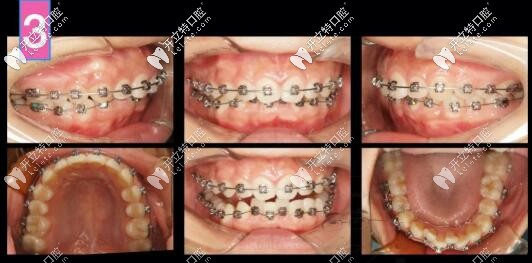

凸嘴自鎖托槽矯正案例

第6個月,上下都排齊了,下頜還是沒有主動跑出來,此時詞用支抗釘整體上牙內收再看看

凸嘴支抗釘內收

齙牙深復合牙齒矯正案例

前牙區(qū)支抗釘安排上!

矯正到34個月,姑娘終于露出久違的燦爛!